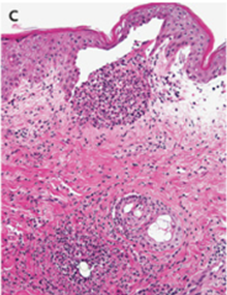

皮膚生検施行。表皮下の膿胞と毛包周囲の好中球浸潤を認めた。

グラム染色陰性、PAS染色陰性、グルコット染色陰性、KOH陰性だった。